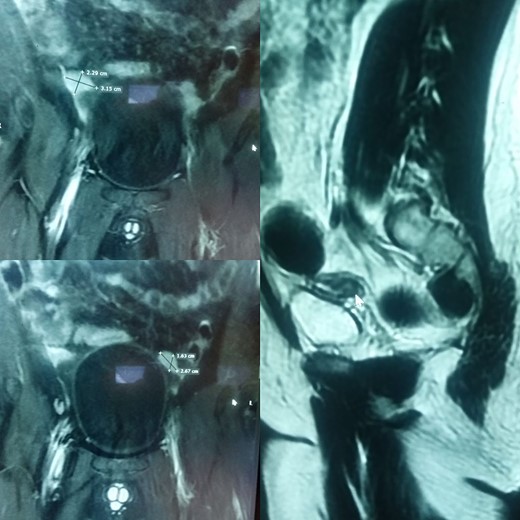

The patient and his family were counseled about the patient’s situation and were informed of the available options. A well-informed consent was obtained from him and his parents for the removal of the rudimentary uterus and both his testes. We used a laparoscopic approach to visualize the presence of testes in the right and left iliac fossas, which were attached to a rudimentary uterus, located posterior to the urinary bladder through the infundibulopelvic ligament (Fig. 2). A round ligament was also seen attaching the uterus to the abdominal wall (Fig. 3). Using the same approach, the infundibulopelvic ligament was ligated followed by the dissection of the round ligament. Uterine vessels were skeletonized and ligated. After adhesiolysis, both the testes and uterus were dissected and placed in an endobag that was then retrieved through the umbilical port and sent for histopathology (Fig. 4).

The uterus and testes were visualized in the lower abdomen by a laparoscope. Testes were seen attached to the uterus through the Infundibulopelvic ligament.